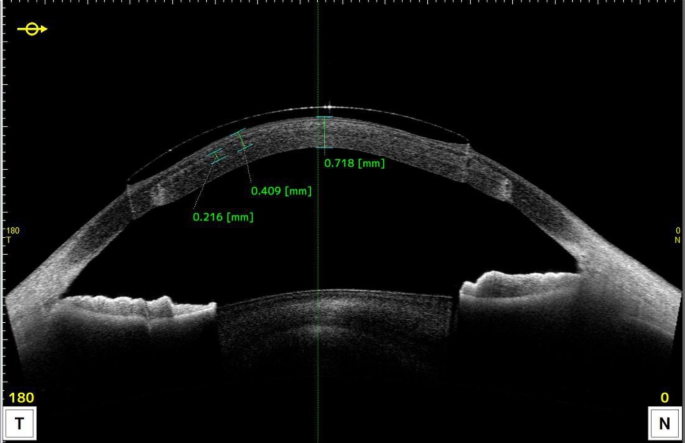

RGP-CLs materials and lens fitting

Corneal Rose-K lenses are used as treatment lenses. The lens diameter is 8.5 ~ 10.4 mm, and the material is Boston XO. The oxygen permeability coefficient (DK value) is 100 × 10− 11(cm2/s) (mlO2/mL mmHg). A diagnostic CL-fitting method was used to finalize the customized CL parameters. The fitting procedure was established in accordance with the guidelines in the Rose K fitting manual. The average K value is selected as the basic curve of the first trial lens. Following a 20-minute adaptation period, both the dynamic and static fit were evaluated. In dynamic fit, the lens was centered adequately on the cornea with good post-blink movement and stability on different gaze movements. In static fit, the central fitting was immediately evaluated with the lens on the center of the cornea after fluorescein staining, and the conical apex of cornea should be slightly in touch with the lens. After the basic curve parameters were adjusted to achieve the best central fitting, the peripheral curve was evaluated and the edge width was adjusted to 0.6–0.8 mm. The trial was conducted repeatedly until an acceptable dynamic and static fit was attained. Upon determining the optimal lens fit, the final power was calculated by performing a spherical over-refraction on the trial lens. The customized lens was observed under the slit lamp microscope to reach a satisfactory fitting: no obvious deviation, good center fitting, and 1.0 ~ 1.5 mm movement (Fig. 1). The fitting relationship between a lens and the corneal surface was examined by panoramic OCT (Tomy Inc., Japan) to show the distribution of the tear film under the lens in different parts. (Fig. 2)